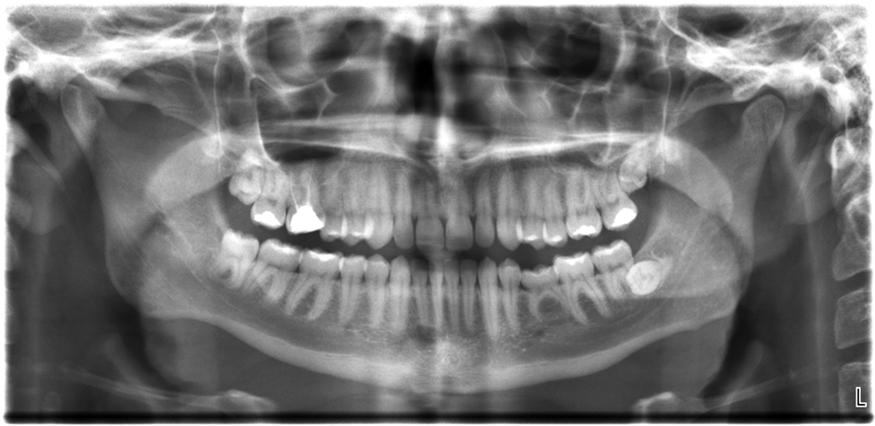

All of us can identify diagnostic uses of X-ray photons. Among these are the universal dental and medical X-rays that have become an essential part of medical diagnostics (see Figure 13.25 and Figure 13.26). X-rays are also used to inspect our luggage at airports, as shown in Figure 13.24, and for early detection of cracks in crucial aircraft components. An X-ray is not only a noun meaning high-energy photon, it also is an image produced by X-rays, and it has been made into a familiar verb—to be X-rayed.

The X-ray image of front view of the jaw, especially the teeth.

Figure 13.24 An X-ray image reveals fillings in a person’s teeth. (Dmitry G, Wikimedia Commons)

The most common X-ray images are simple shadows. Since X-ray photons have high energies, they penetrate materials that are opaque to visible light. The more energy an X-ray photon has, the more material it will penetrate. So an X-ray tube may be operated at 50.0 kV for a chest X-ray, whereas it may need to be operated at 100 kV to examine a broken leg in a cast. The depth of penetration is related to the density of the material as well as to the energy of the photon. The denser the material, the fewer X-ray photons get through and the darker the shadow. Thus X-rays excel at detecting breaks in bones and in imaging other physiological structures, that differ in density from surrounding material. Because of their high photon energy, X-rays produce significant ionization in materials and damage cells in biological organisms. Modern uses minimize exposure to the patient and eliminate exposure to others. Biological effects of X-rays will be explored in the next chapter along with other types of ionizing radiation such as those produced by nuclei.

As the X-ray energy increases, the Compton effect (see Photon Momentum) becomes more important in the attenuation of the X-rays. Here, the X-ray scatters from an outer electron shell of the atom, giving the ejected electron some kinetic energy while losing energy itself. The probability for attenuation of the X-rays depends upon the number of electrons present—the material’s density—as well as the thickness of the material. Chemical composition of the medium, as characterized by its atomic number Z,Z, size 12{Z} {} is not important here. Low-energy X-rays provide better contrast—sharper images. However, due to greater attenuation and less scattering, they are more absorbed by thicker materials. Greater contrast can be achieved by injecting a substance with a large atomic number, such as barium or iodine. The structure of the part of the body that contains the substance, for example, the gastro-intestinal tract or the abdomen, can easily be seen this way.

A standard X-ray gives only a two-dimensional view of the object. Dense bones might hide images of soft tissue or organs. If you took another X-ray from the side of the person—the first one being from the front—you would gain additional information. While shadow images are sufficient in many applications, far more sophisticated images can be produced with modern technology. Figure 13.27 shows the use of a computed tomography (CT) scanner, also called computed axial tomography (CAT) scanner. X-rays are passed through a narrow section, called a slice, of the patient’s body, or body part, over a range of directions. An array of many detectors on the other side of the patient registers the X-rays. The system is then rotated around the patient and another image is taken, and so on. The X-ray tube and detector array are mechanically attached and so rotate together. Complex computer image processing of the relative absorption of the X-rays along different directions produces a highly detailed image. Different slices are taken as the patient moves through the scanner on a table. Multiple images of different slices can also be computer analyzed to produce three-dimensional information, sometimes enhancing specific types of tissue, as shown in Figure 13.28. G. Hounsfield (UK) and A. Cormack (United States) won the Nobel Prize in Medicine in 1979 for their development of CT.